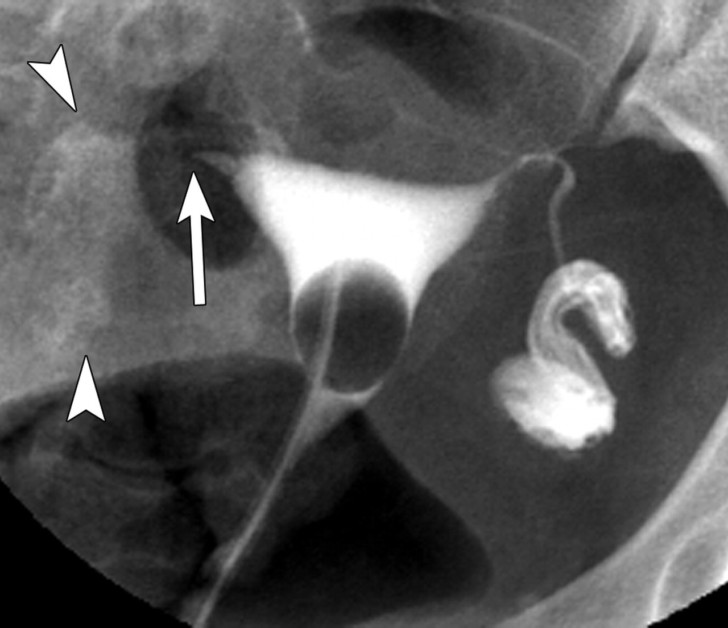

Ультразвуковая диагностика может быть использована для визуализации яичников и фолликулов, содержащих зрелые яйцеклетки. Этот метод более точный, но требует посещения врача и проведения ультразвукового исследования. Ультразвуковая диагностика позволяет определить точное время овуляции и точное количество фолликулов.